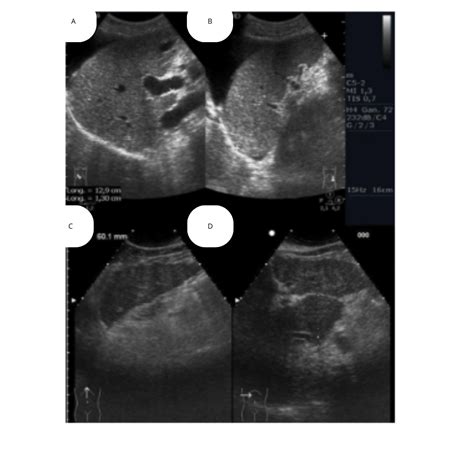

Interpreting the results of a Parenquima Hepatico Izquierdo Ecografia involves analyzing the ultrasound images for any abnormalities in the left hepatic parenchyma. Common findings include:

• Hepatic Lesions: These can be benign or malignant and may appear as cysts, tumors, or nodules.

• Fatty Liver Disease: Characterized by the accumulation of fat in the liver, which can appear as a bright, echogenic pattern on ultrasound.

• Liver Cirrhosis: Advanced liver disease that can show signs of fibrosis, nodularity, and altered liver texture.

• Hepatic Vascular Abnormalities: Such as portal vein thrombosis or hepatic vein obstruction.